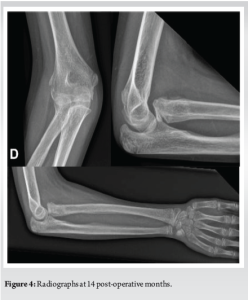

Fourteen months after traumatism, the patient had improved the elbow mobility, with 140° of flexion, only a 5°-lack of extension, full supination, and still 20°-lack of pronation. The radiograph (Fig. 4) showed a good healing of the fracture but persisting slight anterior subluxation of the radial head. The patient and her parents were very satisfied with the evolution of the range of motion and the absence of more severe complications (radial head necrosis, ankylosis).